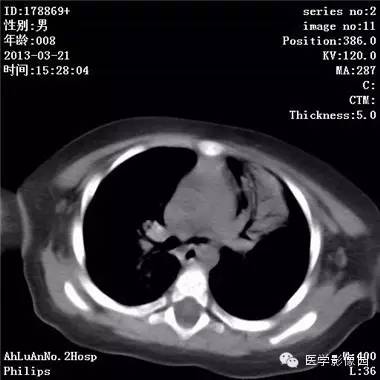

患儿男,8个月,呛咳,发热一周。实验室检查白细胞及中性粒细胞增高。

两肺肺纹理增多、增粗,右肺可见斑片状、片絮状模糊影,边界欠清;左肺上叶见楔形高密度影,内可见支气管征,尖端指向肺门;左肺下叶肺野透亮度增强;另见左肺主支气管内可见块状软组织密度影。

支气管异物(花生米)伴两肺炎症(追问病史,患儿奶奶层于一周前喂食患儿花生米,当时疑似“呛进去”,后来见好了也就没留意)。